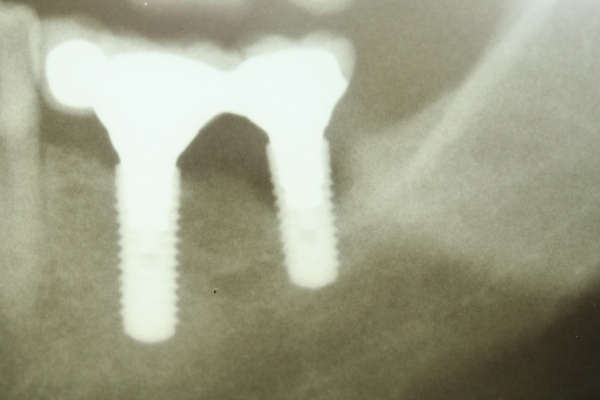

Die Entscheidung für eine regenerative oder eine resektive Therapie (Modul D des Berner Modells) richtet sich nach der knöchernen Defektkonfiguration. Schwarz und Becker (2007) unterschieden in: I. eine horizontale Knochenresorption, II. eine schüsselförmige Knochenresorption, III. eine trichterförmige Knochenresorption und IV. eine spaltförmige Knochenresorption. Wie in der Parodontalchirurgie sollte – soweit vorhanden – mikrochirurgischem Instrumentarium der Vorzug gegeben werden. Die engen periimplantären Verhältnisse bei aufgesetzter Implantatprothetik machen dies notwendig. Der primäre Wundverschluss sollte mit Nahtmaterial 5-0 bis 7-0 erfolgen (Abb. 12, 13, 14, 15, 16).

Dies lässt sich exemplarisch auch im folgenden Fall zeigen: Ein männlicher Patient mit der Diagnose einer generalisierten aggressiven Parodontitis (32 Jahre) befand sich zunächst in einer systematischen antiinfektiösen nichtchirurgischen Parodontitistherapie mit begleitender systemischer Antibiose. An der nachfolgenden unterstützenden Parodontitistherapie nahm er jahrelang teil (2007 – heute) und wies eine sehr gute Compliance auf. Im Oktober 2012 erfolgte durch mich die Implantation regio 34. Ein Jahr post implantationem zeigen sich unverändert kein periimplantärer Knochenabbau sowie klinisch gesunde Gingivaverhältnisse und physiologische Sondiertiefen (Abb. 18).